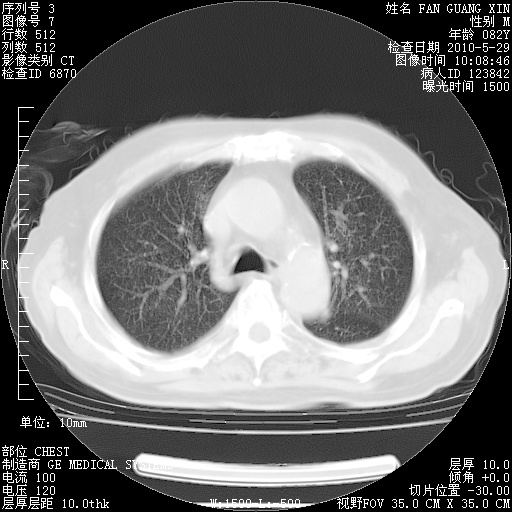

再治疗10天后的肺部CT

阅读此次胸部CT,肺间质渗出性改变较入院时有吸收。目前从体温、白细胞、中性分叶明显增高,肯定存在细菌感染(发生医院感染哦,若无消化道及泌尿系统等感染的依据,肺部感染可能大)。若你院头孢哌酮舒巴坦钠耐药率较高,同意你的方案,若48小时体温仍高,可考虑使用碳青霉稀类抗菌药物,同时可予超声雾化、注意滴数时加大液体量。白蛋白33.30g/L较低哦,需加强营养等支持治疗。